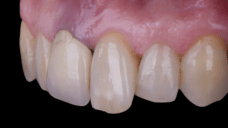

On the same day as the surgery, an immediate-load provisional crown was delivered. This restoration was fabricated in acrylic resin and screw-retained on the implant, following the “one abutment one time” principle. The provisional crown was carefully adjusted to avoid occlusal loading while supporting the peri-implant soft tissue architecture during the healing phase.

The provisional not only satisfied the patient’s functional and esthetic demands but also played a key role in shaping the emergence profile and conditioning the gingival margin. By providing a provisional solution immediately, the patient was able to leave the clinic with a natural-looking smile, avoiding any psychological or social impact associated with tooth loss in the anterior maxilla.